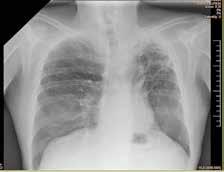

Debido al empeoramiento clínico se solicitó una ecografía de abdomen durante la cual estuvo presente el equipo tratante y en la que se evidenció aumento del líquido libre de aspecto ecogénico sin otras alteraciones. Sin embargo, ante la evolución tórpida y la localización de la contusión abdo minal se comunicó al radiólogo la posibilidad de una perforación intestinal, quien realizó una segunda exploración ecográfica enfocada en las zonas cefálicas y anteriores del abdomen en las que se ubicaría el aire, entonces se visualizaron artefactos en la superficie hepática que sugerían burbujas aéreasextraluminales (Figura 2A). Se realizó una radiografía toracoabdomi nal (RxTA) que confirmó la presencia de neumoperitoneo subdiafragmático bilateral (Figura 2B).

Figura 2. Ecografía con burbujas aéreas extraluminales en la superficie hepática sugestivas de neumoperitoneo (A, flechas). RxTA con neumoperitoneo subdiafragmático bilateral (B, flechas).